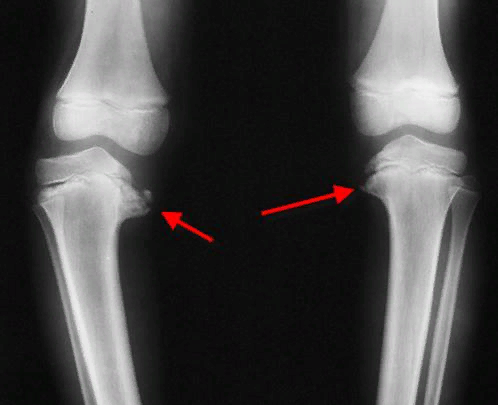

Последствия болезни Блаунта

Болезнью Блаунта (или Эрлахера-Блаунта-Биезиня) называется искривление ног в верхней части голени, преимущественно О-подобное. В редких случаях встречается Х-подобная деформация. Изменения развиваются в берцовой большой кости, поэтому состояние также называют «остеохондрозом большеберцовой кости, деформирующим».

Болезнь связывают с диспропорцией развития конечностей. Так, у костей коленной области есть два участка – ростовые зоны – где, собственно, и происходит рост. Находятся эти зоны на наружной и внутренней поверхностях кости (внешней, иначе латеральной, и медиальной). Уменьшение интенсивности или прекращение роста в медиальной зоне на фоне нормального развития латеральной ведет к деформации конечности.